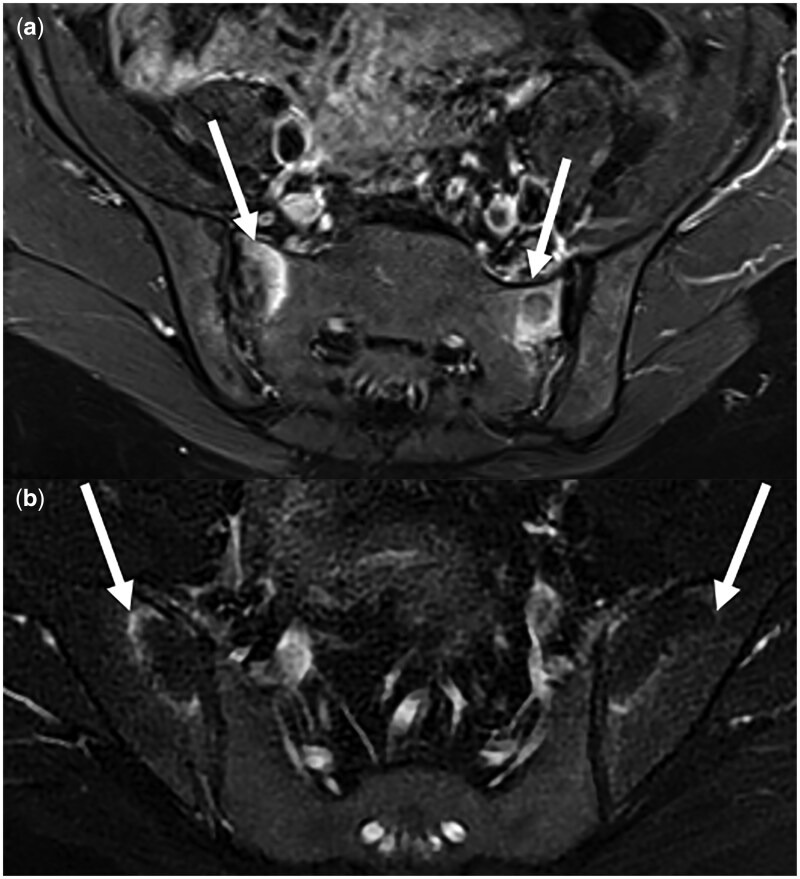

Results: All patients were female with a mean age of 34 years. BME was observed in 66% (19/29) of OCI patients. BME in OCI was mainly located in the anterior-middle quadrant (43.48%). OCI patients had significantly more than one delivery (P = 0.0094, McNemar test), even if OCI was found in four nulliparous patients (15%). OCI patients experienced significantly more pain (P = 0.0026, McNemar test).

Conclusion: OCI is an entity found in both pregnant and non-pregnant young women. SIJ BME was found in two-thirds of OCI patients. OCI is a significant cause of BME and should be carefully considered by clinicians when dealing with a patient with low back pain in order to avoid misdiagnosing spondyloarthritis in the presence of BME of the SIJ.